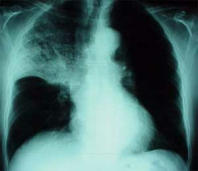

Blood group A has a chronic mucus problem that provokes that the members of type A are always in danger for infection diseases: Sinusitis, bronchitis and pneumonia.

Example: x-ray photo of a pneumonia with shadowed medium and upper part of the lung (right).

-- pneumonia, x-ray photo: http://www.doktor.ch/krankheiten/lungenentzuendung.html